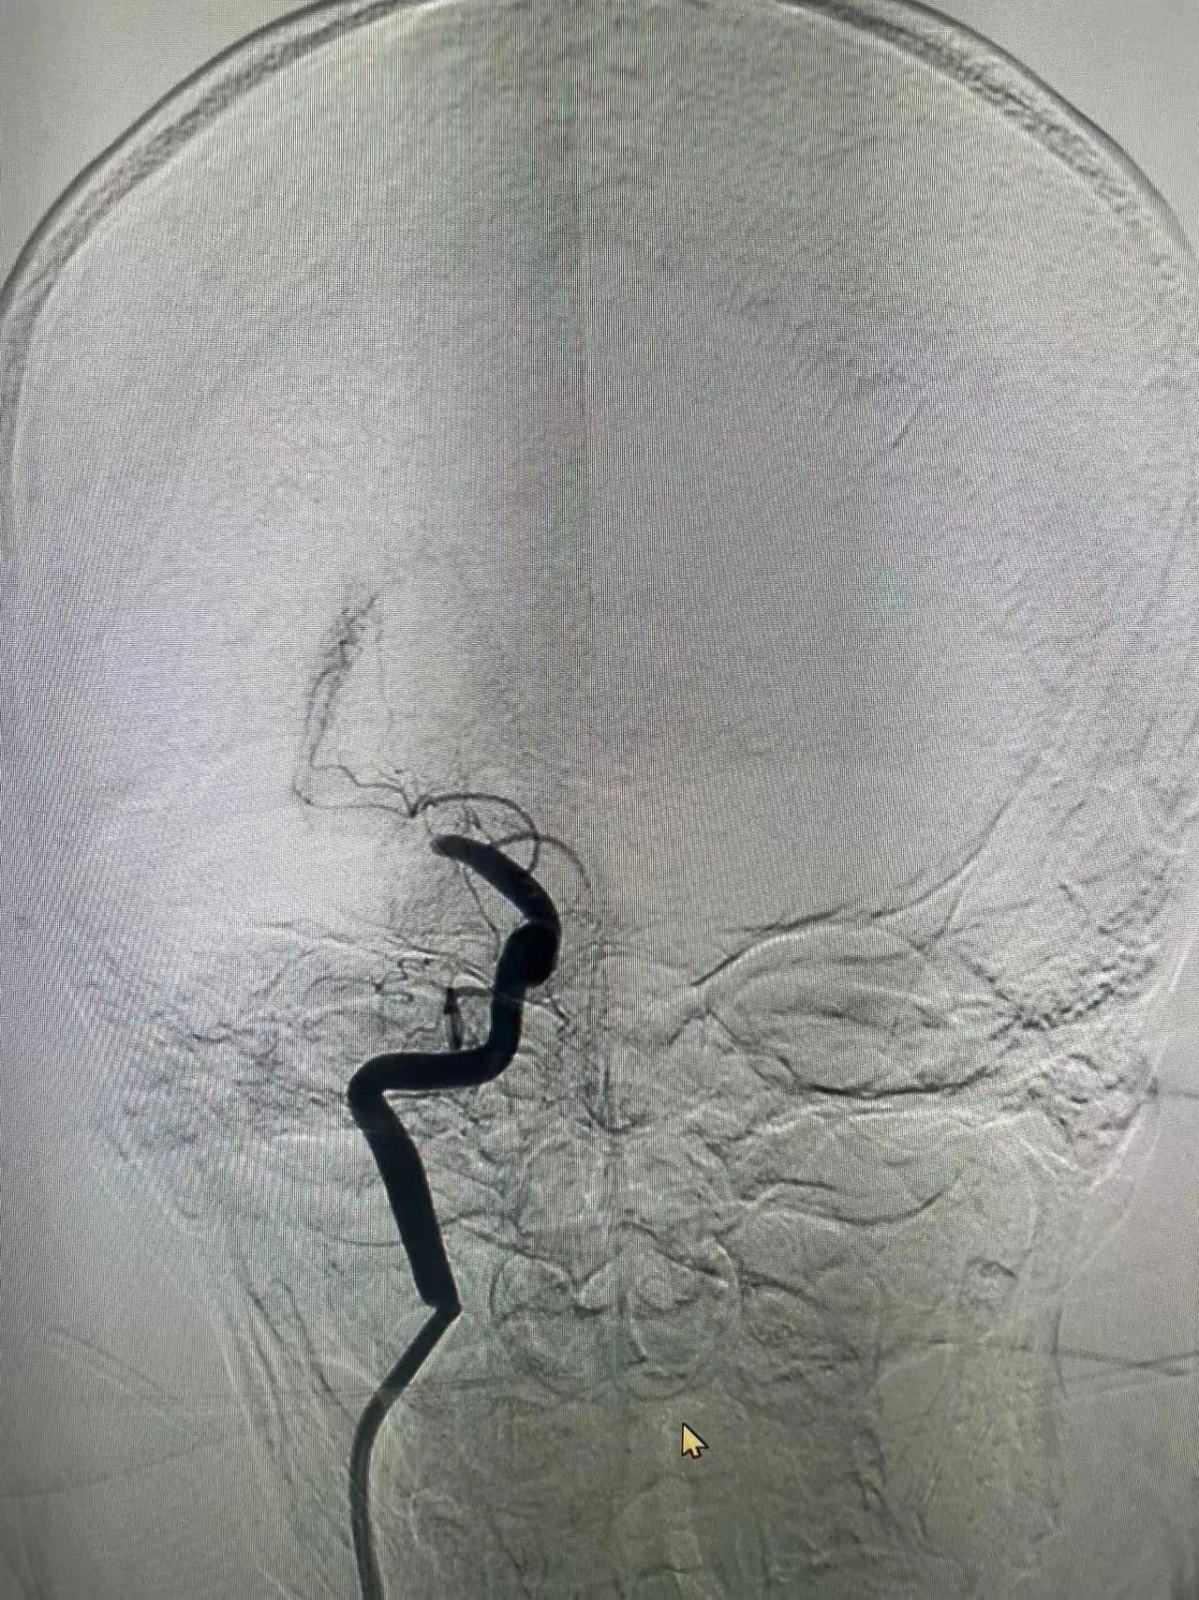

在导管室的无影灯下,一场与死神的较量悄然展开。家属的信任目光化作医者无畏的动力,造影剂显影瞬间印证了术前判断——右侧大脑中动脉完全闭塞。介入专家精准操控抽吸导管,成功取出新鲜血栓,然而复查造影显示血管仍存在重度狭窄。

"准备2.0/15mm球囊,立即行血管成形术!"随着导丝精准穿行,球囊在狭窄段完美展开。当造影剂再次流淌的刹那,原本淤滞的血管重现通畅,台上监护仪的波形跳动与患者的肢体活动同步恢复。